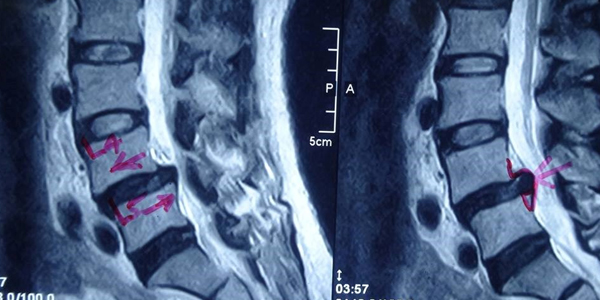

– Cộng hưởng từ (MRI):

+ Cộng hưởng từ là công cụ lý tưởng để đánh giá tổn thương về mô mềm và sự chèn ép thần kinh trong trượt cột sống vùng thắt lưng – cùng. Trên phim cộng hưởng từ, có thể phát hiện các nguyên nhân gây chèn ép thần kinh: đĩa đệm thoát vị, dây chằng dày, các tổ chức xơ sẹo, hẹp lỗ ghép,…

Hình 2: Mô phỏng hình ảnh trượt cột sống trên MRI